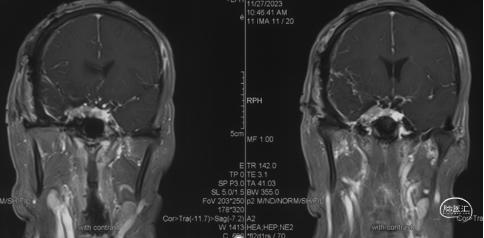

术前影像学检查

头颅MRI+增强